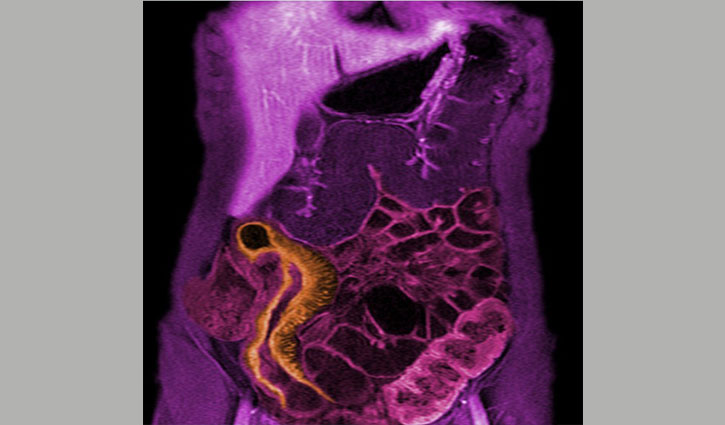

ক্রোনস রোগে আক্রান্ত রোগীর একটি এমআরআই ছবি। এই রোগের উপসর্গ হল পেটে ব্যথা, রক্তাক্ত ডায়রিয়া, জ্বর এবং ওজন হ্রাস।